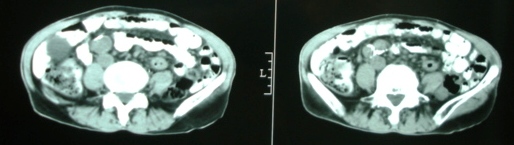

m/72y,皮肤巩膜黄染6个月。

ct意见:1、胆总管结石并肝内胆管、胰管扩张。

2、胆囊结石并胆囊炎。

胆总管结石左侧高密度影是什么?

1)支持楼主意见。2)胆总管结石左侧高密度也应该是胆总管结石。

1)支持楼主意见。2)胆总管结石左侧高密度可能是胆囊管结石。